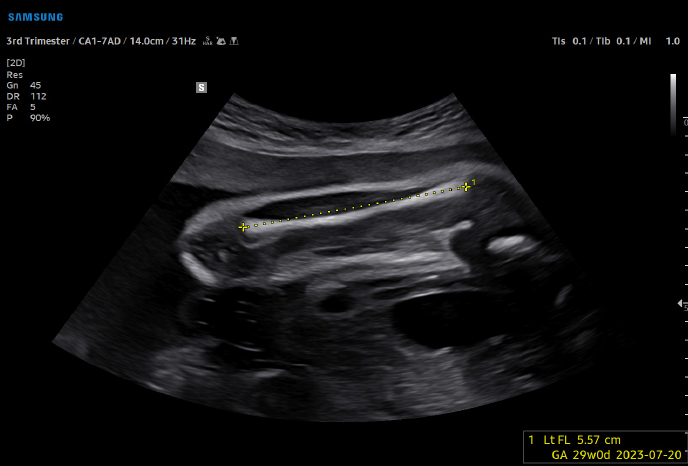

Samsung V6 Ultrasonic

고급 실시간 3D(4D)로 시각화 가능

고급 도플러 기능으로 심혈관 평가 및 이상 감지

이미지 해상도 극대화, 노이즈 최소화로 장기의 경계부를 선명하게 관찰

저강도 초음파 기술로 신체 조직 위험 최소화

연속적인 모니터링으로 고양이 심장초음파에 최적

복부간담도계, 비장, 소화기계, 비뇨기계, 부신, 생식기계, 복강 림프절